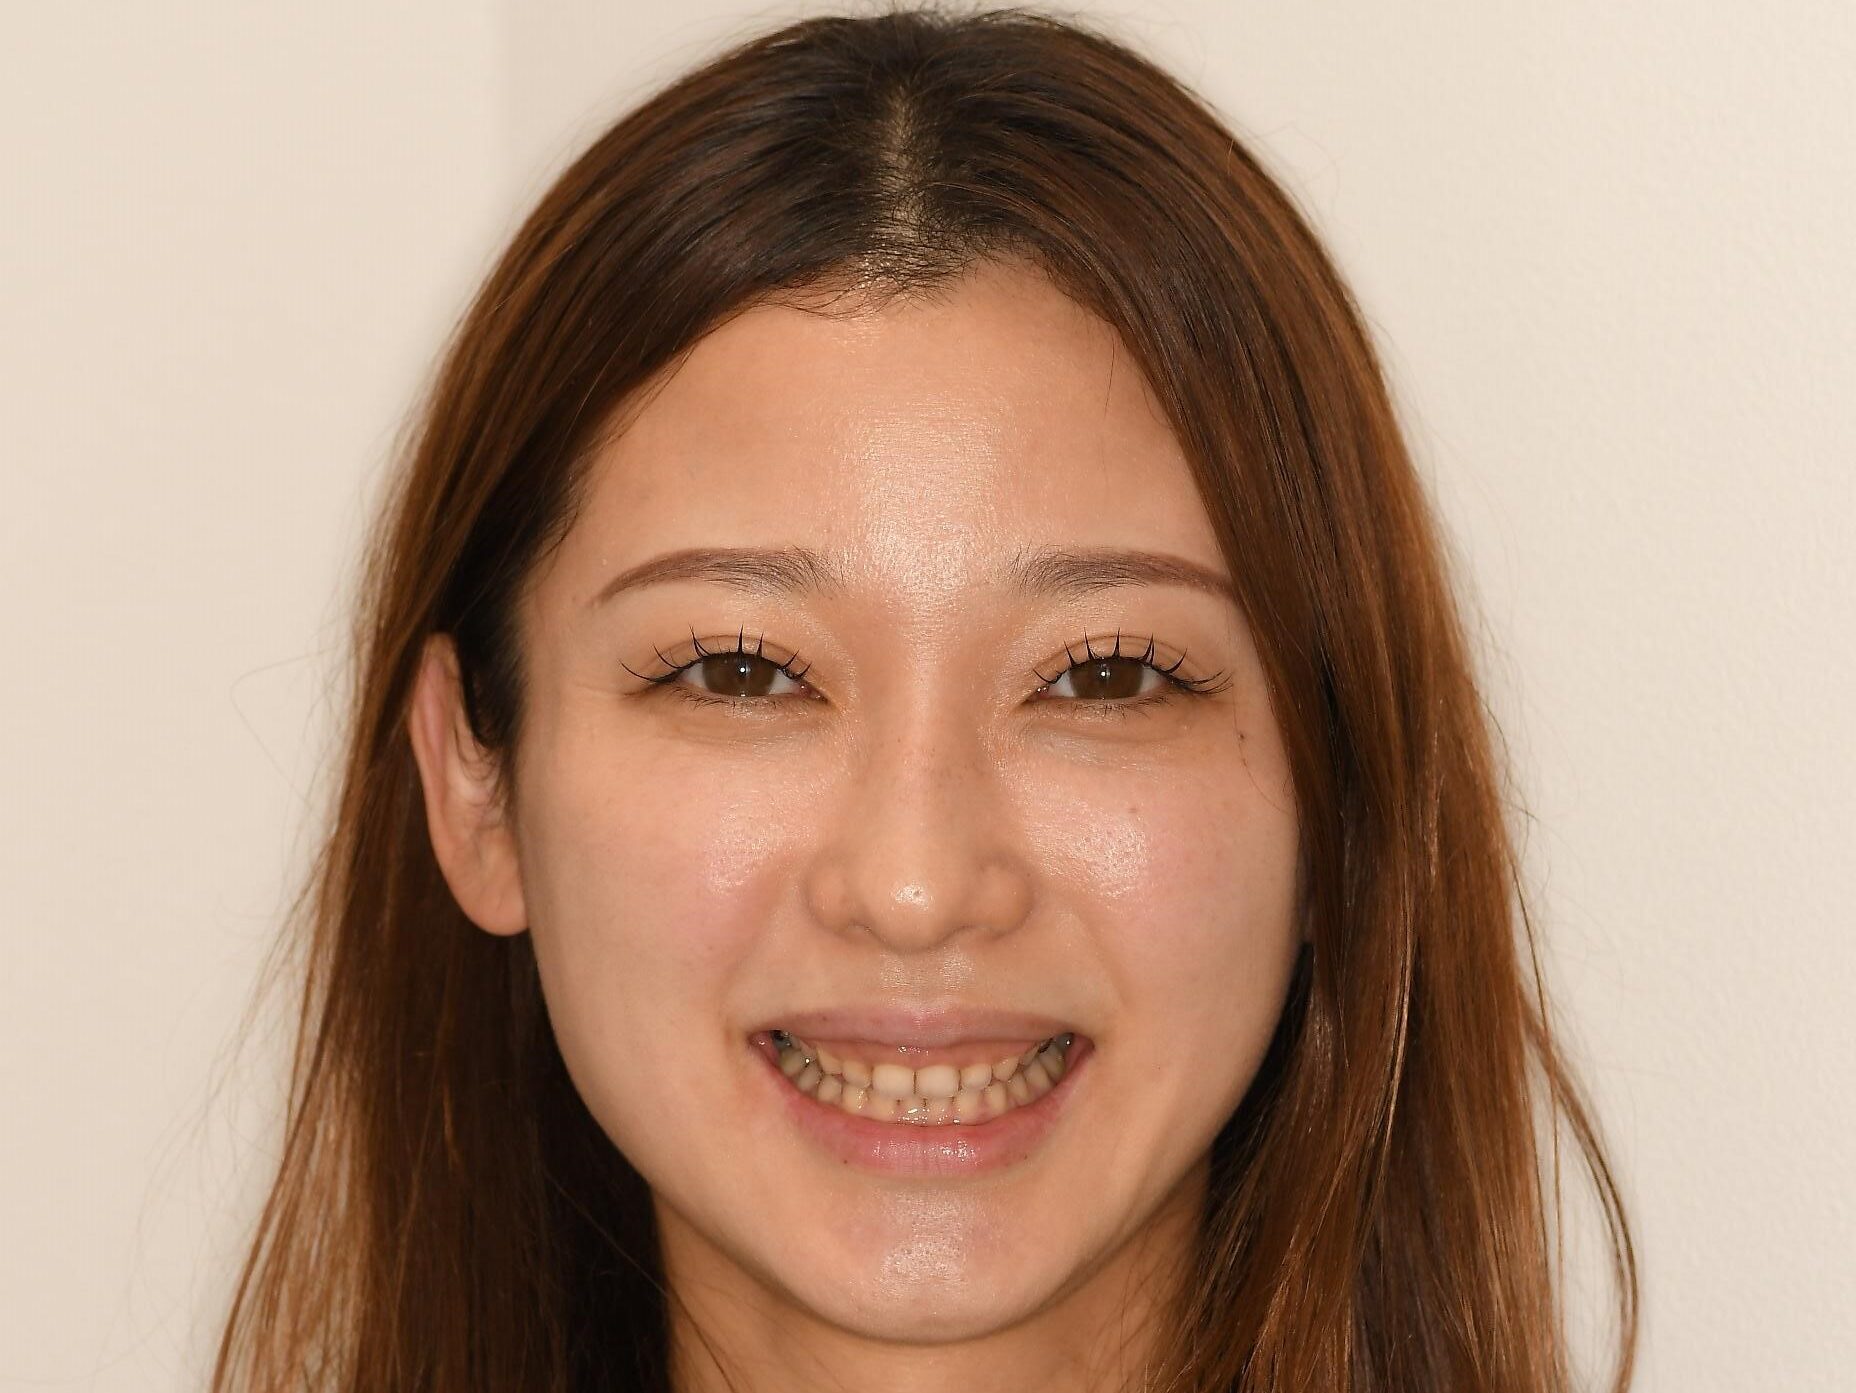

ガミースマイルの悩みから解放された症例

〜審美的歯冠長延長術(審美CL)〜

ガミースマイルは、「笑ったときに歯ぐき(歯肉)が大きく見えてしまう状態」のことを指します。

人前で笑うのに抵抗が出てしまったり、写真で口元を閉じてしまうほどコンプレックスになる場合も少なくありません。

今回ご紹介する患者さんも、まさにその一人でした。

■ 治療前のお悩み

患者さんは、

「人と話すとき、いつも口を手で隠してしまいます…」

とお話しされていました。

笑顔になりたいのに、無意識に手が口元に行ってしまうほど、ガミースマイルが長年の悩みだったそうです。

治療前

■ 術後の変化と患者さんの声

治療後

治療前後比

術後の腫れも最小限で、回復も良好。

そして何よりも、笑顔が見違えるほど自然に✨

チェック時には患者さんから、

「もう手で隠さずに笑えるようになりました!」

「こんなに変わるなら早く相談すればよかったです」

と、とても嬉しいコメントをいただきました。